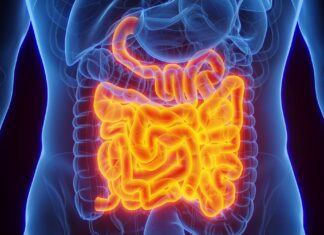

Подвійний охоронець кишечника: як білок інтелектин-2 захищає організм від інфекцій

Нове дослідження, проведене вченими з Массачусетського технологічного інституту (MIT), виявило складну біологічну систему безпеки в травному тракті людини. Дослідження показує, що специфічний білок, відомий...